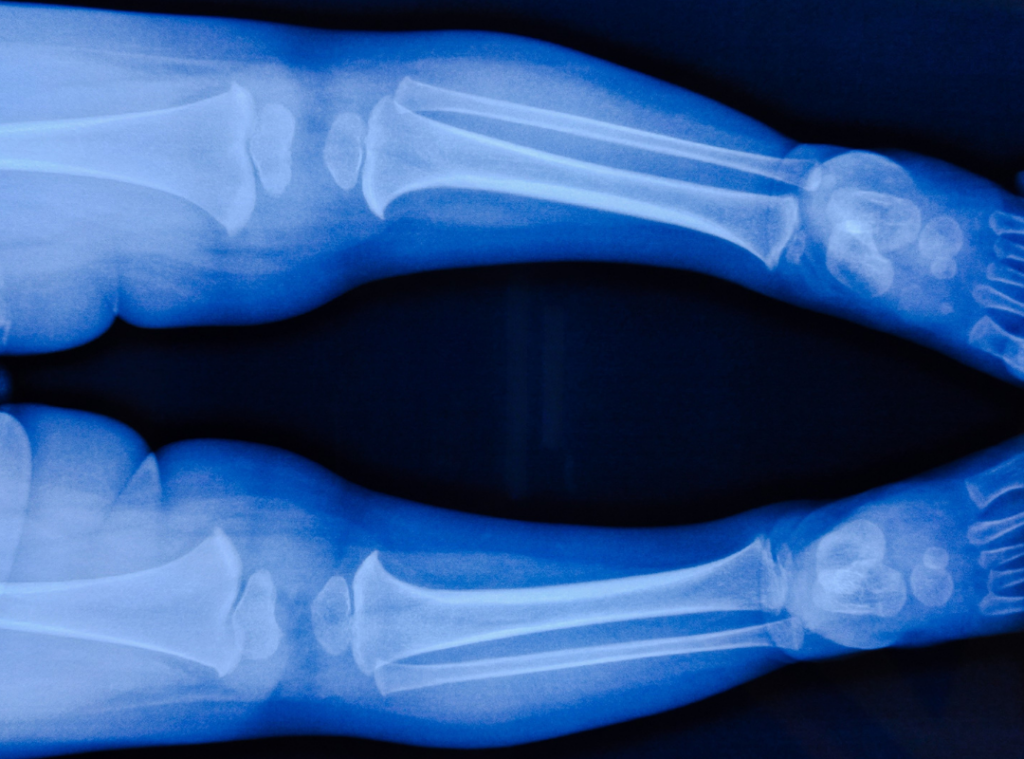

- Medical Documentation: Diagnostic records, including blood tests showing low phosphate levels or X-rays showing under-mineralized bones.

This is a critical distinction that many emergency rooms missed. Fractures caused by rickets often show "under-mineralization" on an X-ray, meaning the bones look thinner or less white than healthy bones. Child abuse fractures typically occur in healthy, dense bone. We work with medical experts to review your child's X-rays to prove that the fractures were a result of nutritional deficiency, not physical trauma.